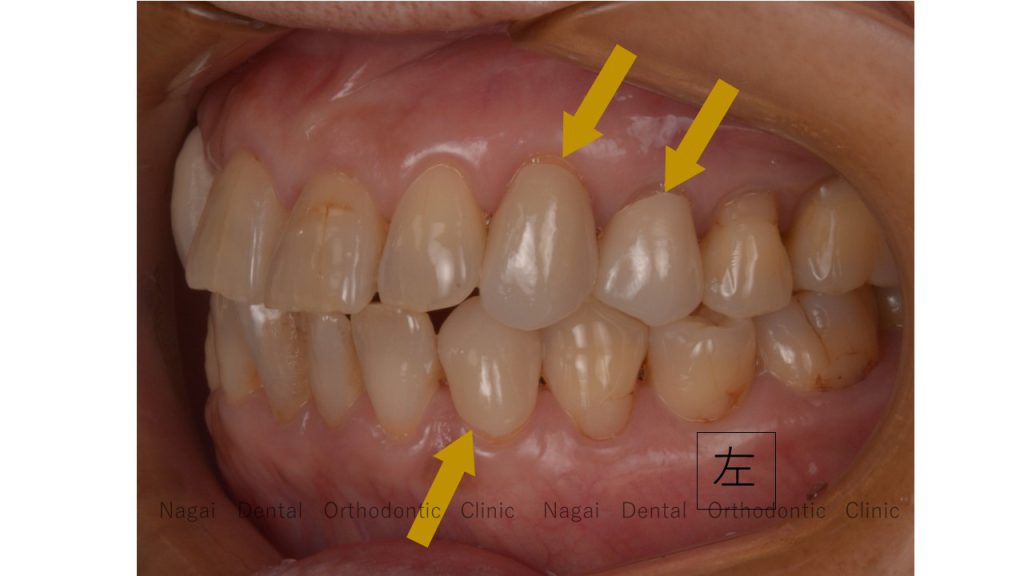

Bさんの歯列は向きがおかしく、奥歯以外は噛めていません。

Bさんは奥歯6番・7番でしか噛めていないので、

●左上3番・4番をセラミック

●左下3番 セラミック

左右共に、3番から5番にもしっかりとした噛み合わせを作ることを考えました。